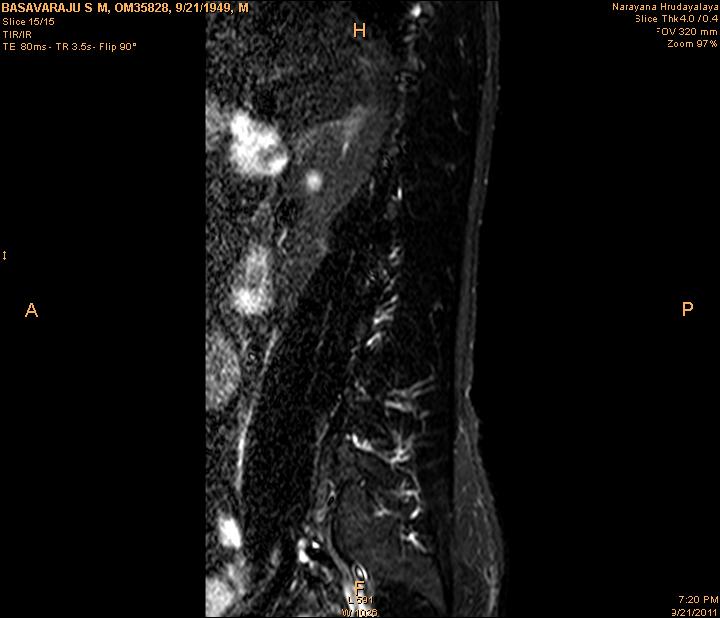

In order to show the proposed method in more detail, the algorithm is tested with other test images. The first row of Fig. 6 shows the original MRI image of thoracic spine with different views. The second row of Fig. 6 shows the same image enhanced using histogram equalization. Third row of Fig. 6 presents the MSR based enhancement scheme. Fourth row of Fig. 6 indicates Chao’s method of image enhancement. Finally, the reconstructed images using the proposed method is shown in fifth row of Fig. 6. Again, it can be seen from the results presented that the image enhancement using the proposed method is superior compared to other methods. This is evident from the image quality assessment presented in Table 1 using AWE and DWE.